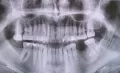

2 недели назад отколол небольшой кусок от правой нижней пятерки (не уверен, правильно ли назвал, считал от середины, если считать сзади, то он третий). Болей не было, но решил посетить стоматолога во избежание негативных последствий. Зуб начали сверлить под предлогом «кариеса», поставили пломбу, нерв не удаляли. Начиная со следующего дня, боль в зубе постепенно нарастала, чувствовалась пульсация и давление, повторный визит откладывал, считая перечисленные симптомы временными.

Спустя 4-5 дней почувствовал резкую кратковременную (несильную) боль в основании зуба, по ощущениям было очень похоже, как будто какая-то жидкость растекается последовательно по основаниям других зубов (по направлению к передним). После этого пульсировать и болеть начали и соседние зубы, особенно передние. Постепенно это ощущение начало распространяться и по направлению от передних зубов в сторону языка. Это стало последней каплей, поэтому повторно посетил стоматолога (уже другого), который удалил нерв в той самой пятерке, почистил каналы и поставил пломбу. После данных процедур зуб стал беспокоить гораздо меньше (прошло 3 дня), но не могу сказать, что перестал беспокоить вообще.

Меня действительно беспокоят сохранившиеся ощущения пульсации в передних зубах и по направлению от них к языку. Второй день пью антибиотик (бисептол). Видимых припухлостей и вообще каких-нибудь изменений в ротовой полости не заметил.

Обратитесь к другому врачу. Думаю, что диагноз уже периодонтит, и методы лечения должны быть другие.